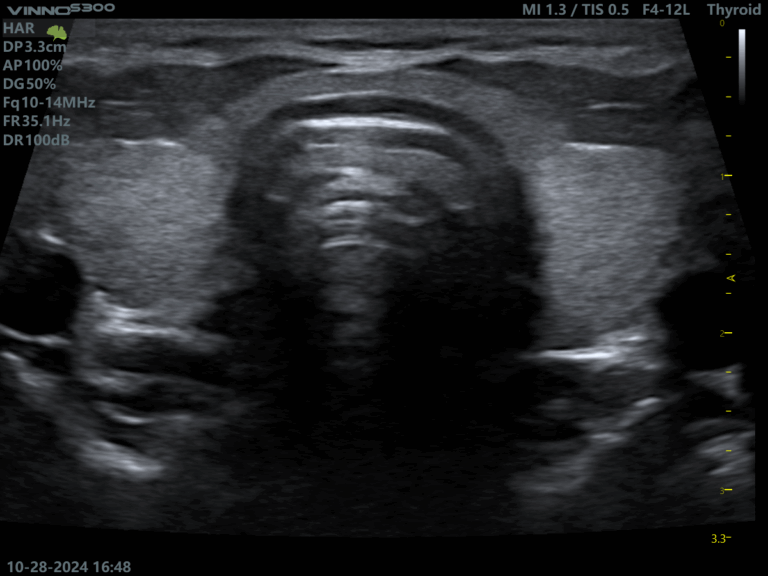

Ecograf VINNO S300: performanta si inovatie in practica medicala

Ecograful VINNO S300 este un model mai recent, creat pentru a raspunde cerintelor medicilor care doresc atat calitate superioara a imaginii, cat si functionalitati inteligente.

Caracteristici principale:

- Imagini clare 2D si evaluare precisa a fluxului sanguin

- Modul Ultrasense pentru optimizare automata

- Design ergonomic, potrivit pentru examinari frecvente

- Ideal pentru aplicatii musculo-scheletice, gastroenterologie si obstetrica

- Reduce timpul de examinare prin automatizare

- Raport excelent pret-performanta